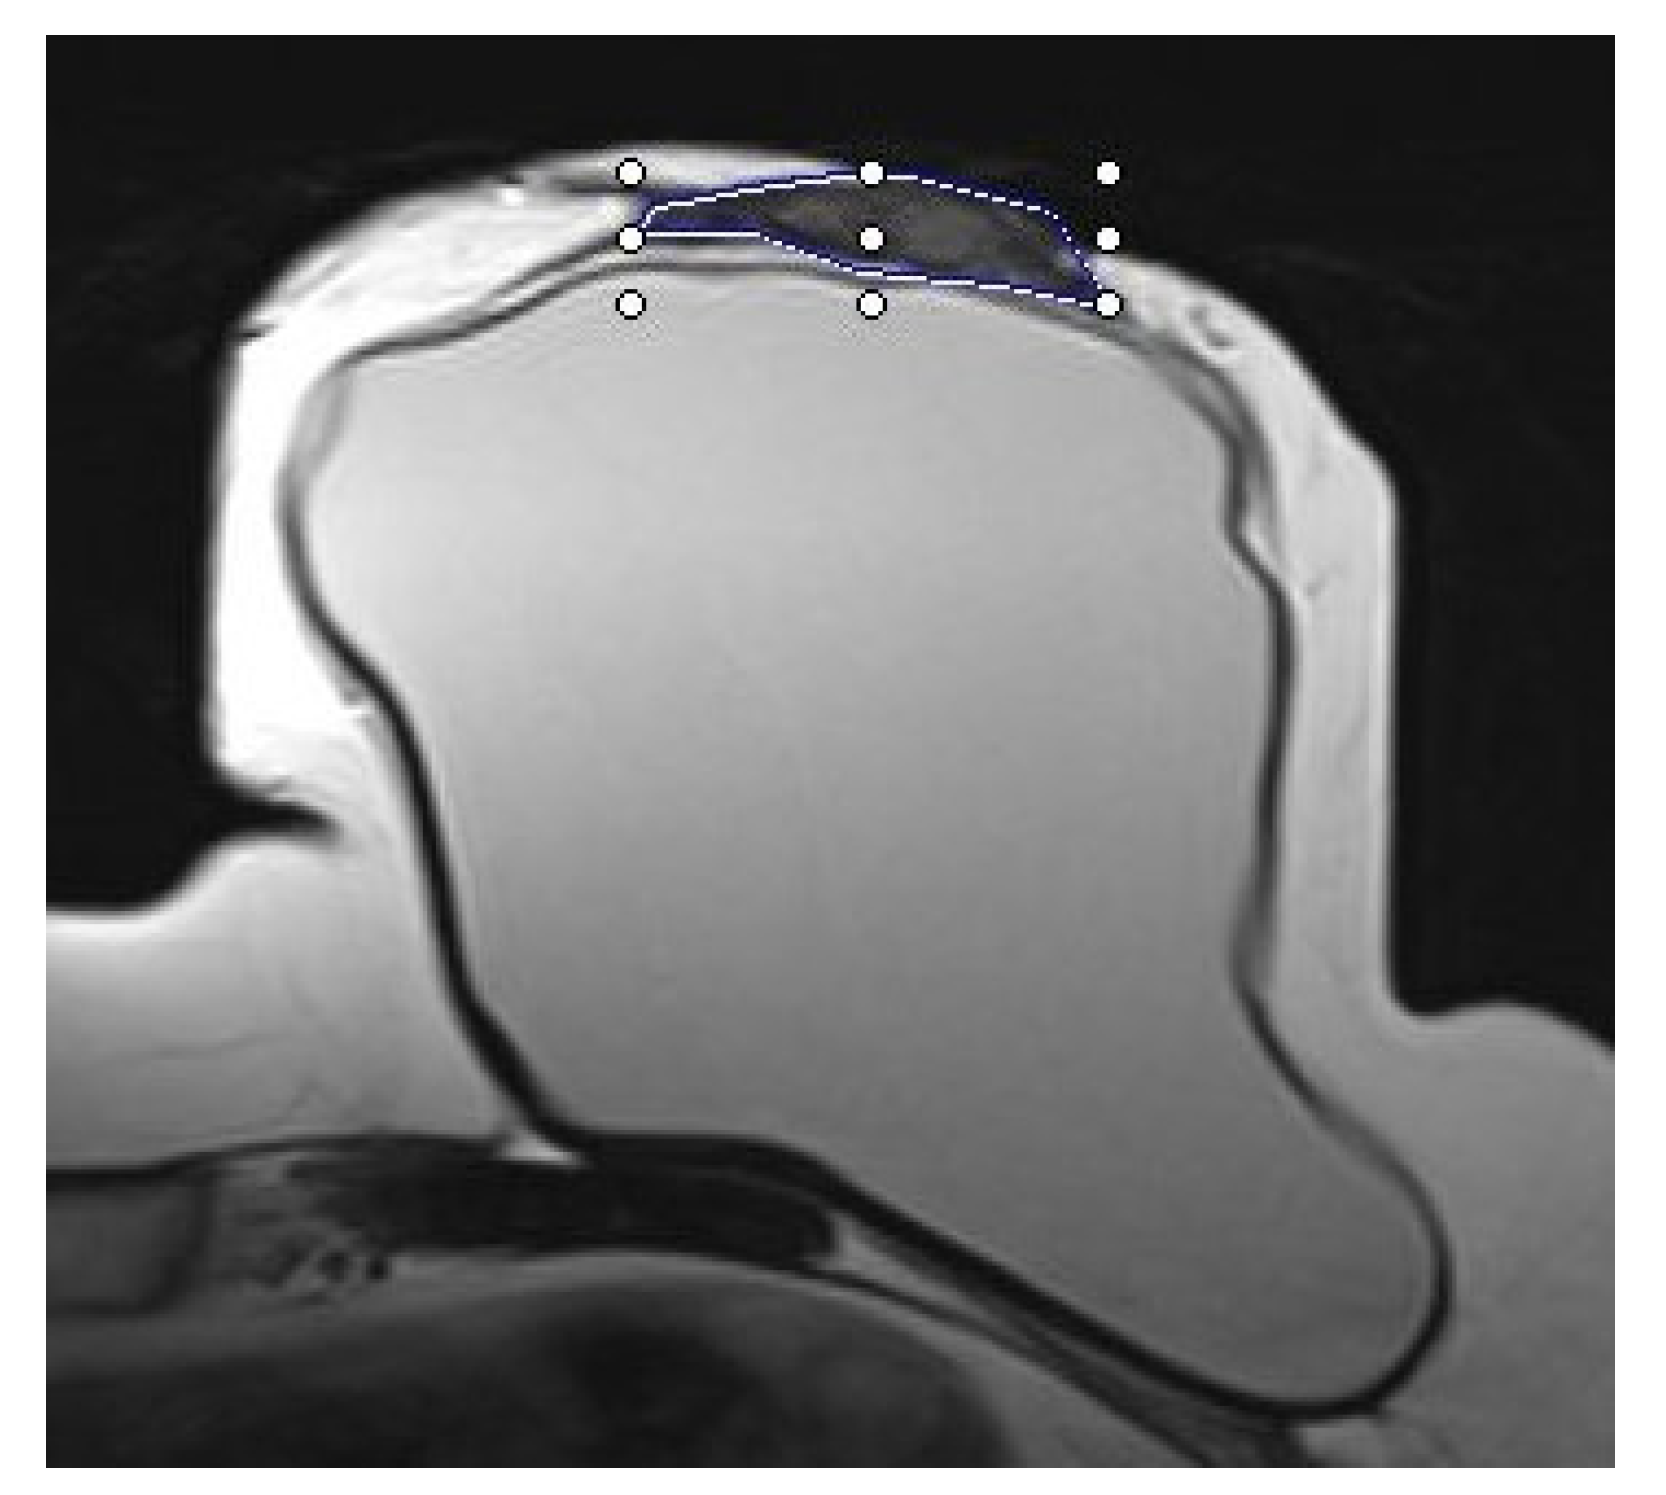

2.3. MRI Data Analysis

- Postoperative breast volume;

- Volume of the residual glandular tissue.